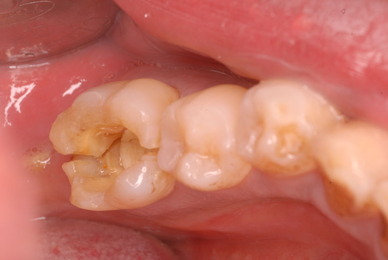

これぞ医師の姿ではないでしょうか。![11229551_834920046584649_8659418848563116234_n[1]](https://livedoor.blogimg.jp/netdental/imgs/c/0/c098deb4.jpg)

![11053897_834920076584646_6691737990508884178_n[1]](https://livedoor.blogimg.jp/netdental/imgs/b/b/bb679b8f.jpg)

![11010956_834920133251307_8897824032330972564_n[1]](https://livedoor.blogimg.jp/netdental/imgs/c/2/c2aa3129.jpg)

![10403096_834920093251311_4823181277198290695_n[1]](https://livedoor.blogimg.jp/netdental/imgs/b/7/b77edc79.jpg)